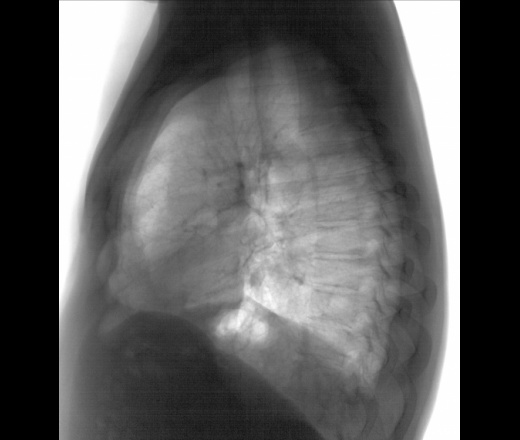

Мужчина 40 лет. Диагностическая  флюорография. Пришел на контроль, был поставлен диагноз 01.11.25 пневмония с\д, справа, в другой клинике. Смущает тень, которая видна только на задней проекции, в верхней доле справа, что это может быть? И еще, как считаете, есть выпот слева?

На левом боковом этой тени не видно